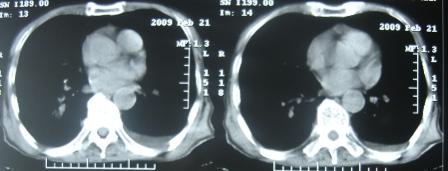

xx 男 63岁 发热 家属描述有时高热 有时低热 抗酸杆菌阴性 于2月21号 胸片及ct

右肺上叶干酪性肺炎并两肺支气管播散。

考虑右肺上叶干酪性肺炎并支气管播散。

楼主  :谢谢大家发言  我和大家考虑的一样干酪性肺炎并播散